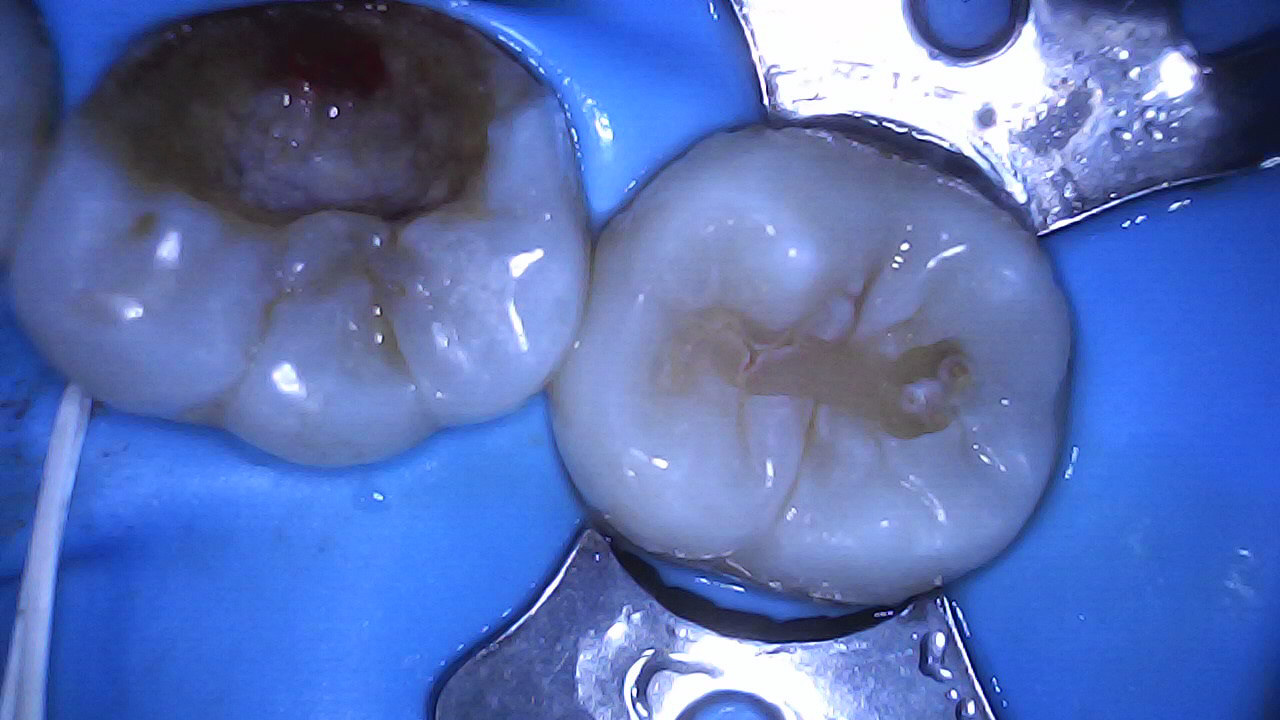

Selective caries removal with help from caries dye

36 restores temporarily with Filtek Supreme A2B. Fuji VII to monitor pulp response 3 months